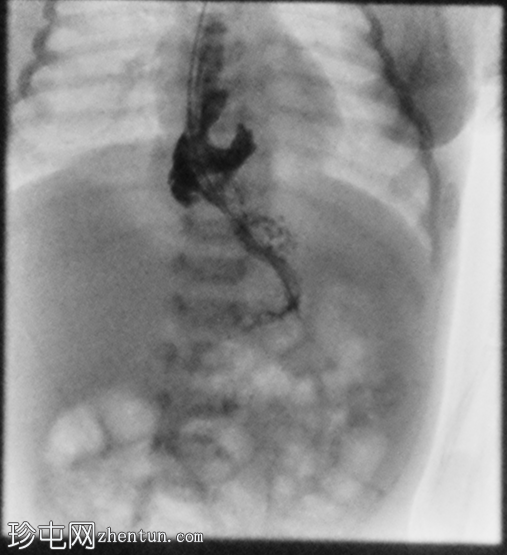

3.png

正位

胃部初始显影,并立即反流至食管裂孔疝。在其近端可见管径正常的远端食管。十二指肠降部和横部显影较弱,左上腹可见数段管径较小/部分减压的近端小肠显影。

延迟1小时拍摄的X线片显示食管裂孔疝和胃部仍有造影剂残留,造影剂远端扩散受限,很可能是由于造影剂用量较少所致。充满气体的肠袢外观正常,乙状结肠内可见气体,直肠内未见气体。